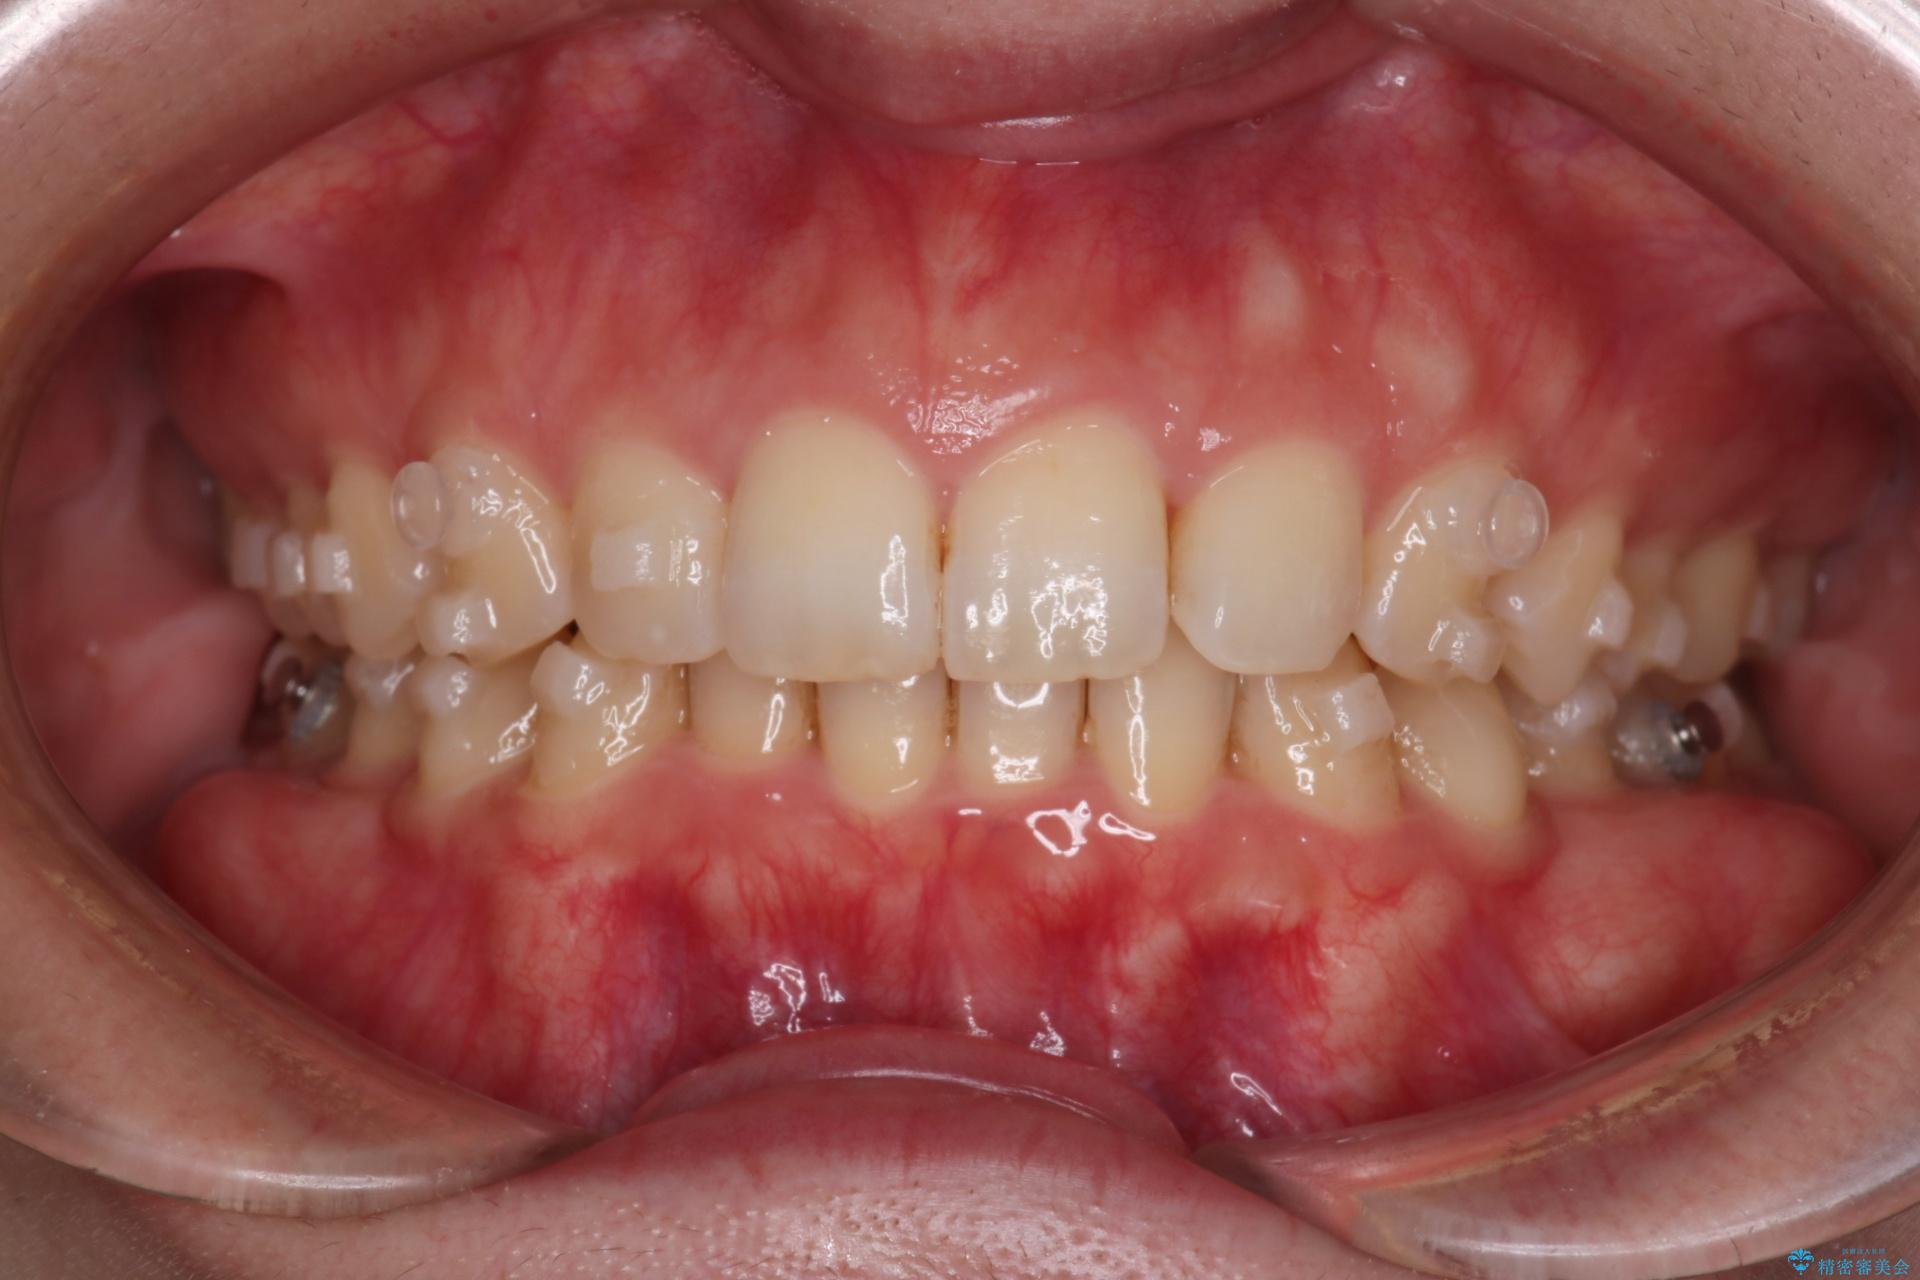

- インビザライン・ワイヤー装置(クリア装置)

右側臼歯部の咬合改善のために、臼歯部のみ部分的なワイヤー矯正を行い、咬合改善がみられてからインビザラインにて全体的な矯正を行なっていく治療計画を立てました。

噛み合わせをよくするために、ワイヤー矯正とインビザライン矯正のどちらの期間も必要な箇所にゴム掛けを行いながら治療を行いました。

ゴム掛けを頑張っていただいたので、噛みあわせも改善され綺麗な歯並びになりました。